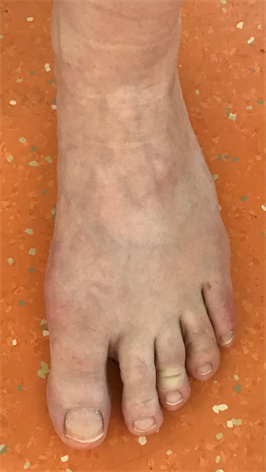

Figure 27. Patient Nr. 5: Hallux valgus with pronation, elevation, malrotation and pathological DMAA.

Figure 28. Patient Nr. 5: Correction of all components, only partial contact of bone partners, additional FDL Transfer II for a flexible hammertoe II.

Figure 29. Patient Nr. 5. Result after 8 years.

Figure 30. Patient Nr. 5: View of the foot preoperative, Pronation 40˚.

Figure 31. Patient Nr. 5: View of the foot postoperative, Pronation corrected.